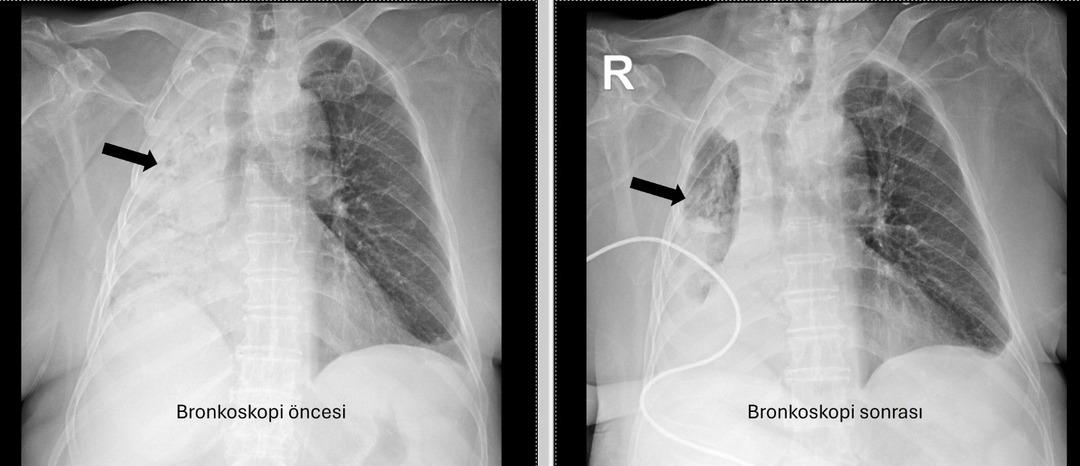

Denizli'de yaşayan 78 yıllık kadın ve emekli bir öğretmen yakın zamanda akciğer enfeksiyonu nedeniyle hastanede idi. 1 ay önce gittiği hastanede bronkoskopinin yapılmasına rağmen, sorunun tespit edilmediği öğrenildi. Yaşlı kadın, sağ akciğerin Pamukkale Üniversite Hastanesi'nin belirlenmesine tamamen kapatıldığı hastaneye gitti.

Pau Ökr Hastaneleri Göğüs Hastalıkları Bölümü. Prof.dr. Üye Dr.Köksel Altōiş Ergur, sağ akciğerler tarafından yapılan sınavlar için tamamen kapatıldı. Acil bronkoskopi planlandı ve prosedür derhal gerçekleştirildi. Dr. Altenishık ergur, hava yollarını incelerken çok yoğun ve karanlık bir salgılama ile esnek bir “bronkoskop” (esnek, katlanabilir), ancak hava yollarının derinlemesine temizlenmesini takiben, bir olaydan dolayı dönüştürüldüğünü ve berrak olduğunu, bir olaydan dolayı dönüştürüldüğünü açıkladığını açıkladığını açıkladığı açıktır. Vücudun açık olduğu açık olduğu açık olduğu açık olduğu açıktı. genel anestezi ile yapılmıştır;

Prof. Alküzek Ergur, hastanın trakeasının nasıl engellendiğini açıkladı: “Havayollarında sıvı emen aspiratörün gücünü kullanarak nesneyi çıkarmak mümkün oldu. Hastanın hastanın tekrar yediği pizzada yediği pizza için daha önemli olduğu öğrenildi.